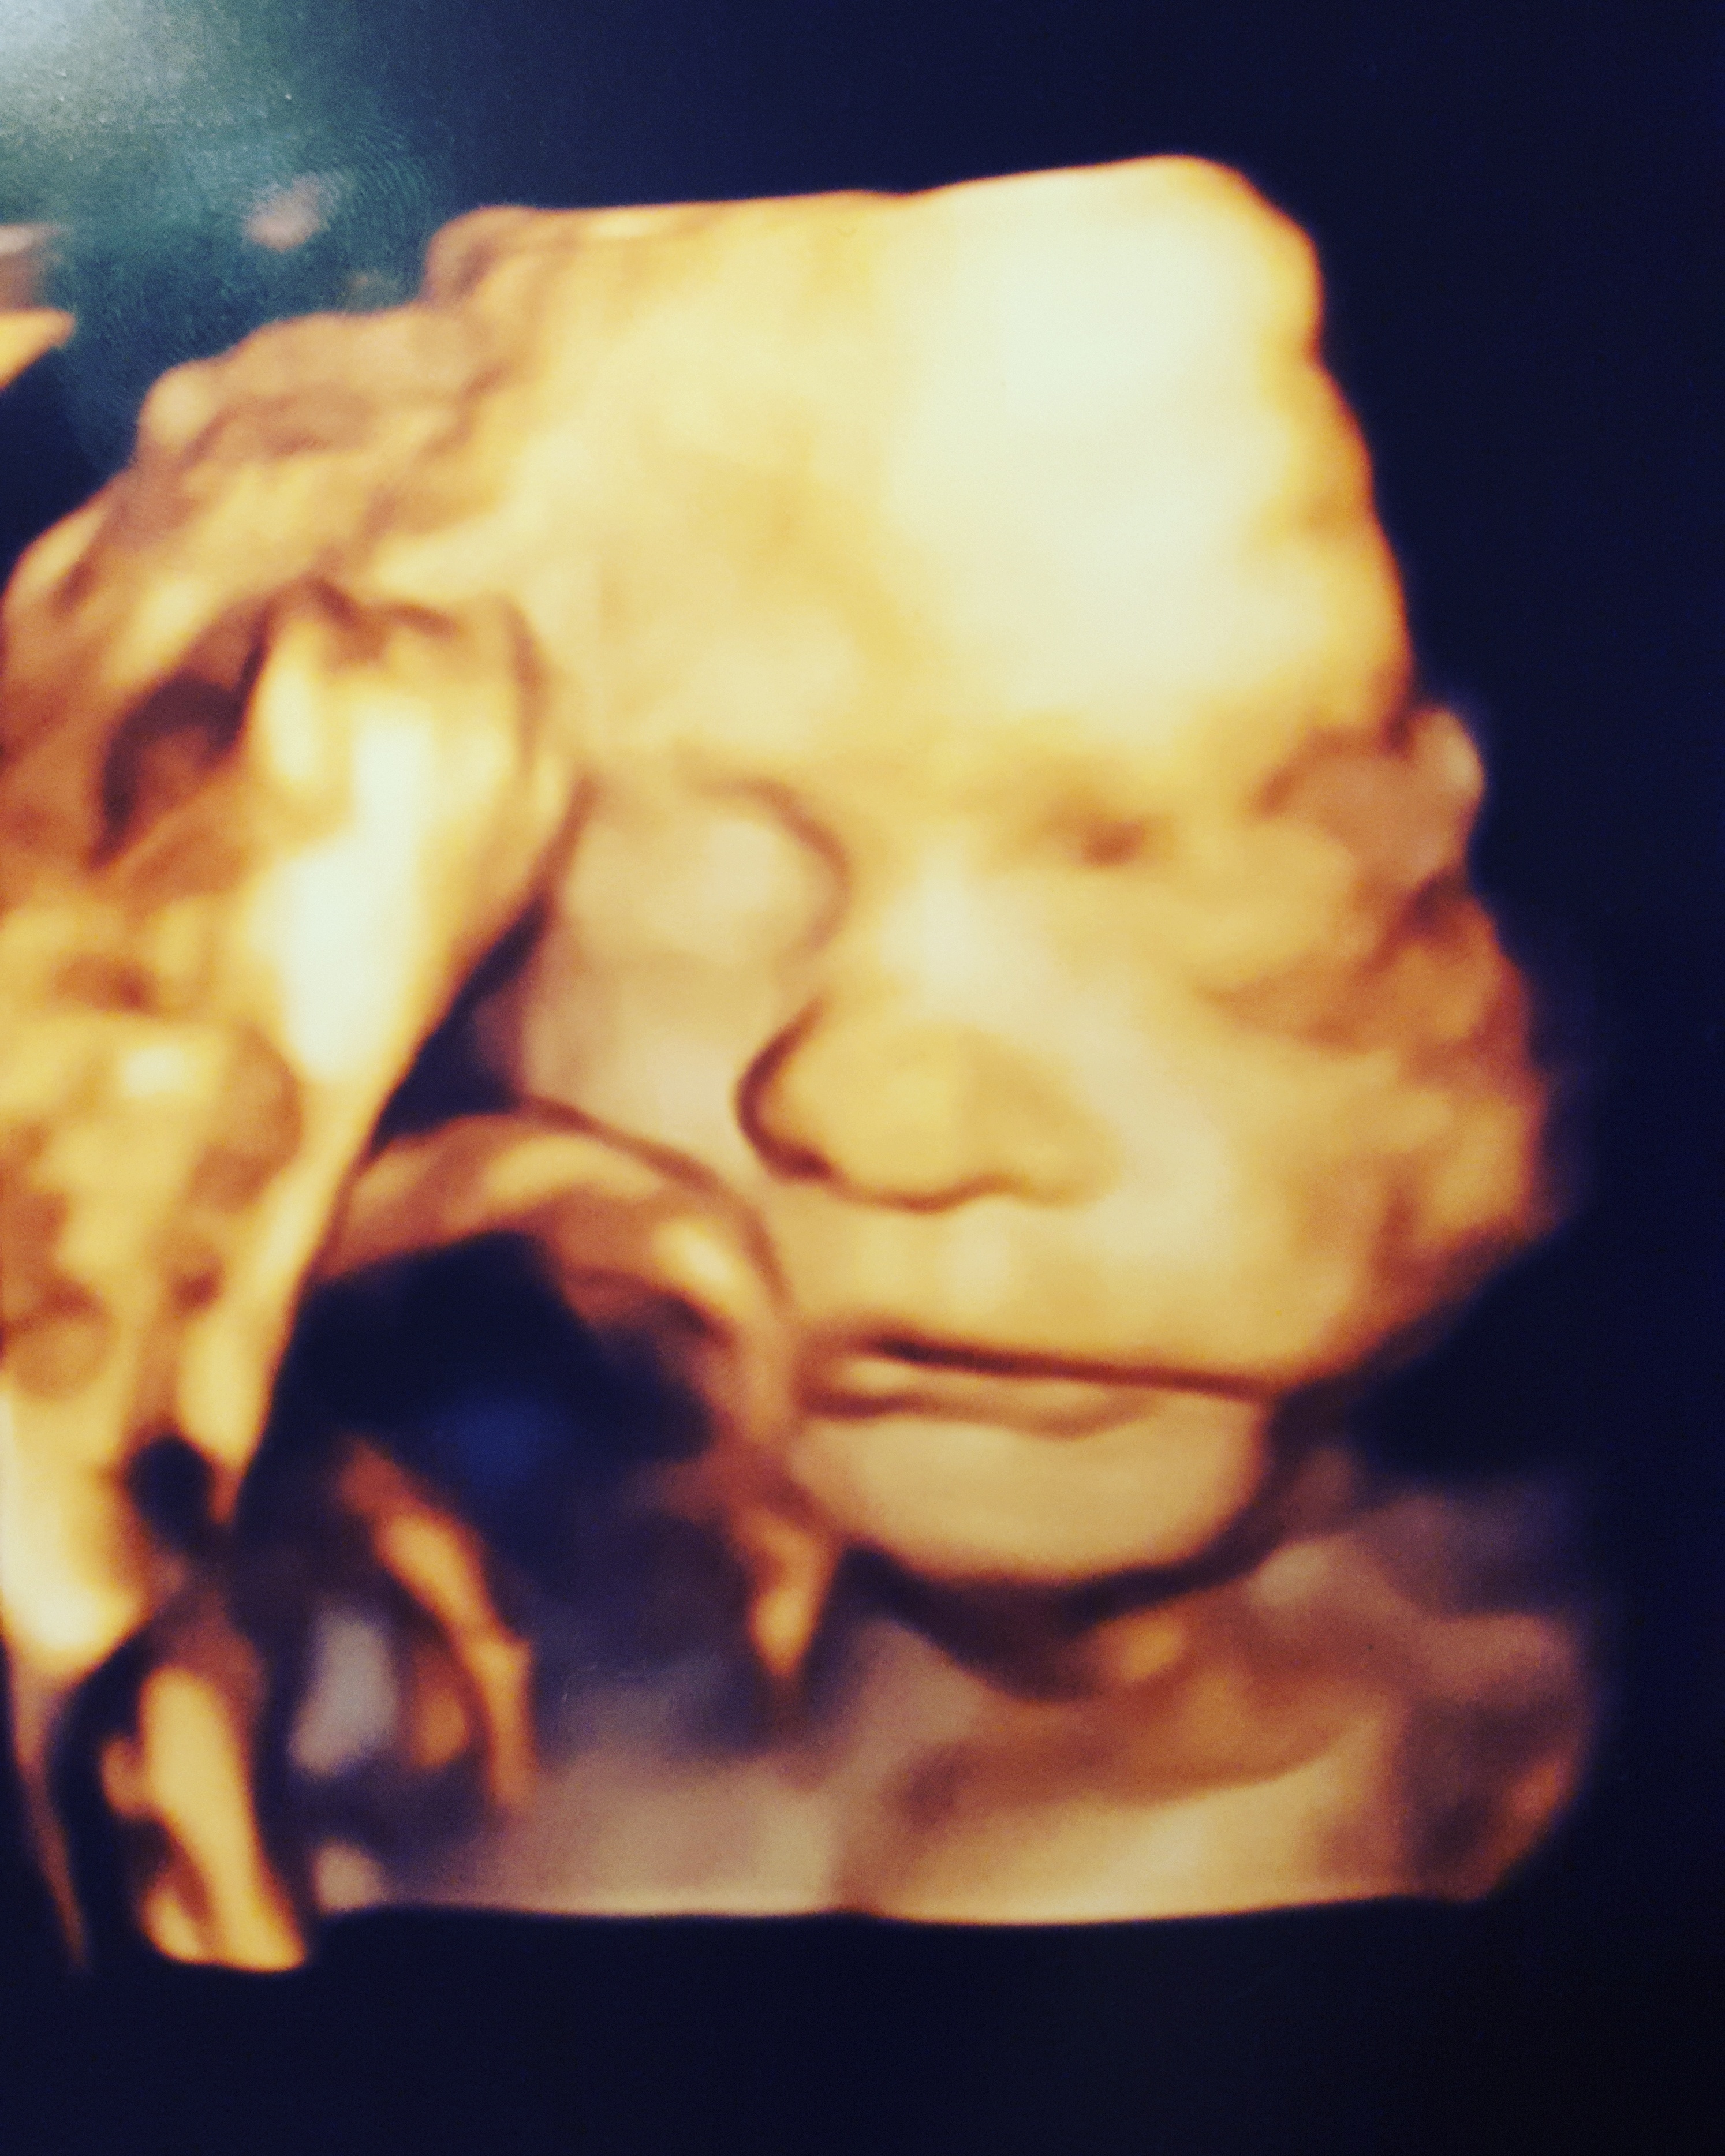

3rd Tri Ultrasound Sharing

Re: 3rd Tri Ultrasound Sharing